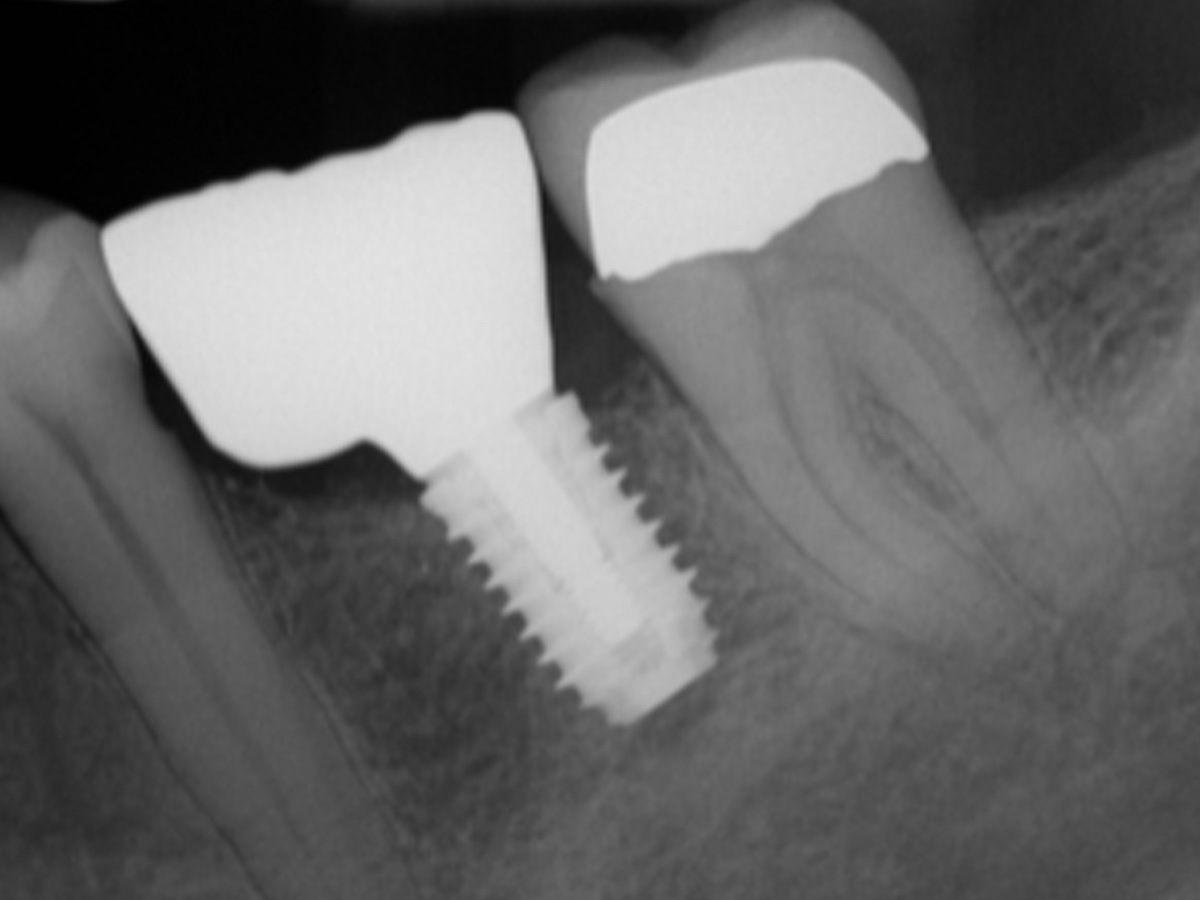

Bei den Abb. 10 und 11 handelt es sich um das Einzelzahnröntgen der Situation und das klinische Bild der implantatgetragenen Versorgung.

Augmentation nach fünf Monaten (röntgenologisch).

Abbildung 11